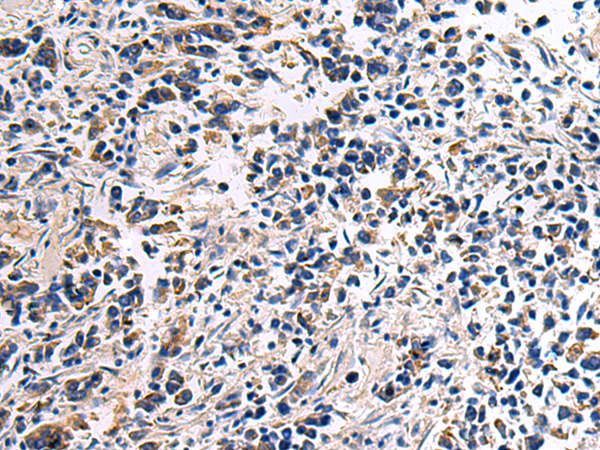

分类: 科研抗体货号: P06442别名: IL-34; C16orf77应用: WB,IHC反应种属: Human